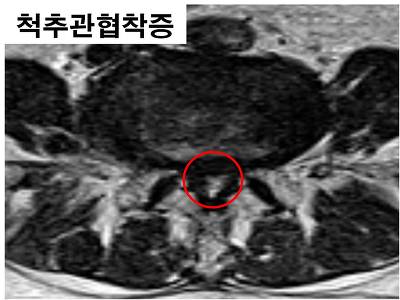

척추관협착증

척추관협착증은 척추의 근육과 인대의 퇴행으로 인해 척추의 황색인대의 부종으로 인해 척추관이

좁아지게 되어 발생하게 됩니다.

그에따라 척추관내에 있는 신경이 인대의 부종으로 인한 압박으로 하지의 감각이 무딘 증세가 나타납니다.